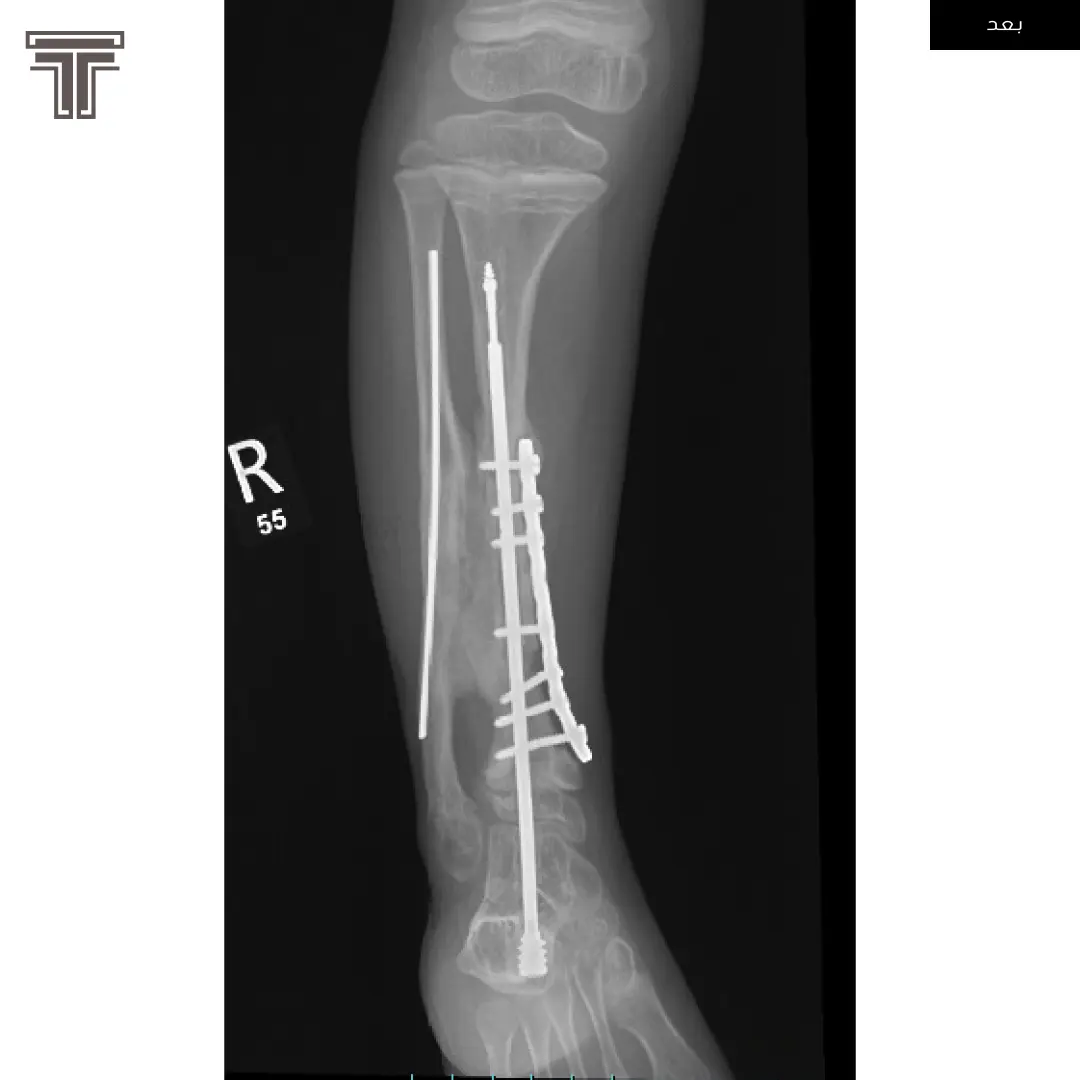

عندما تهمل خلوع الورك الولادية لعمر كبير يصبح علاجها وارجاعها صعب ويتطلب عملية استبدال للمفصل. وفي مثل هذه العمليات وتحديدا في استبدال مفاصل خلوع الورك الولادية يتطلب تقصير في طول الفخذ لتجنب المضاعفات.